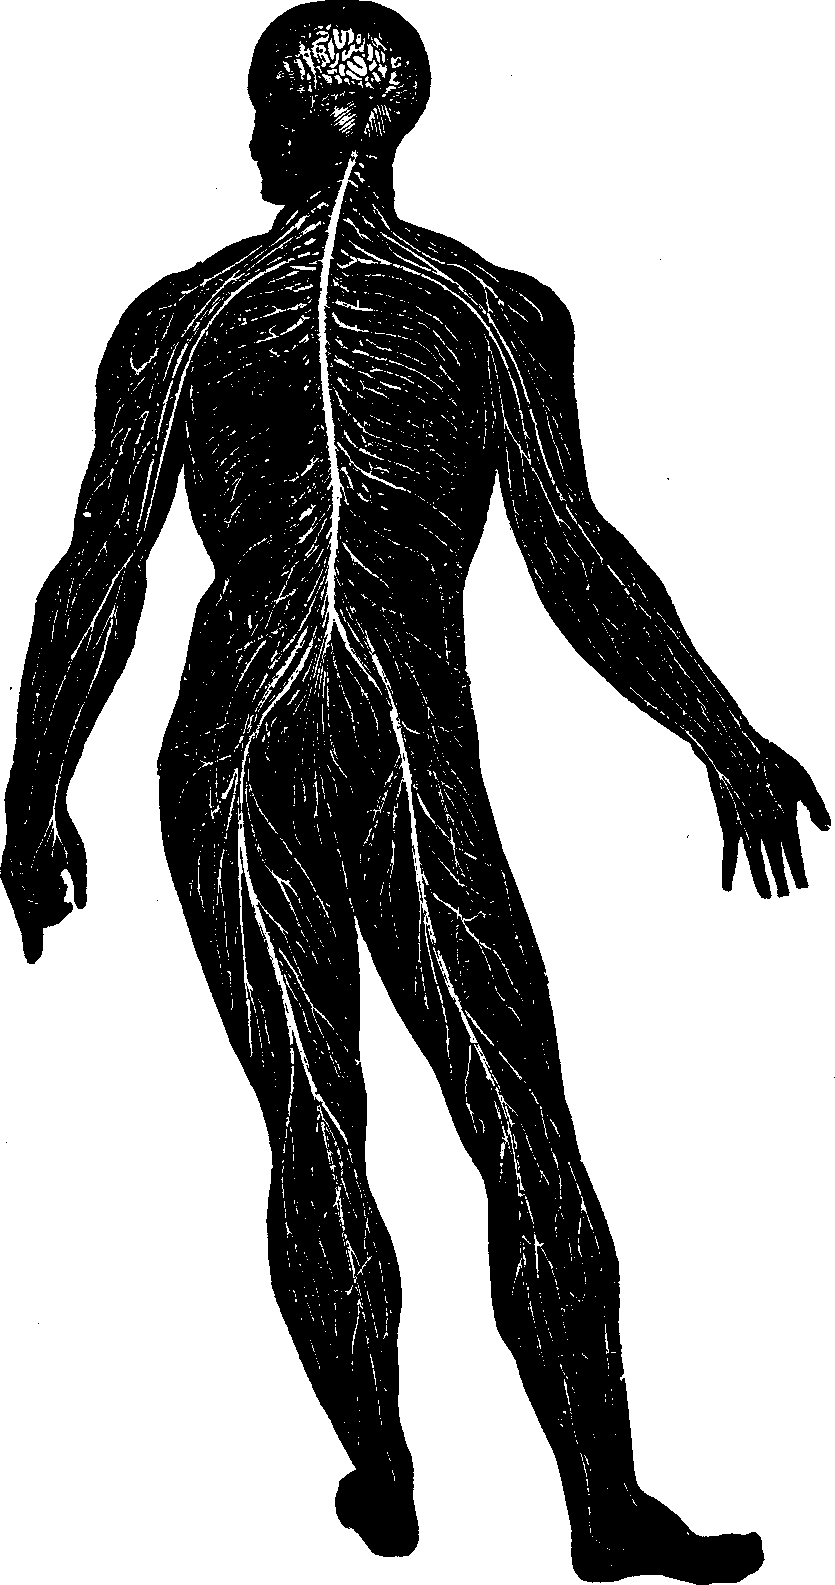

20]The Nervous Tissue is of two kinds: The gray, which is

pulpy and granulated, and the white fibrous tissue. The Adipose